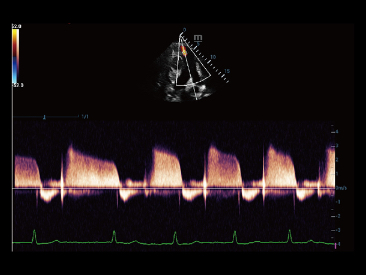

Naast de hoogwaardige beeldvormingskwaliteit verbetert de Resona 7 tevens de klinische onderzoeksmogelijkheden met de revolutionaire V Flow voor vasculaire hemodynamische evaluatie, en de intelligentste vlakacquisitie van een 3D-gegevenssets voor de diagnose van het foetale, centrale zenuwstelsel. Met zijn combinatie van de meest intu?tieve, op vingerbewegingen gebaseerde multi-aanrakingsbediening en alle essenti?le klinische functies loopt de Resona 7 voorop in de nieuwe golven van ultrasoundinnovatie.